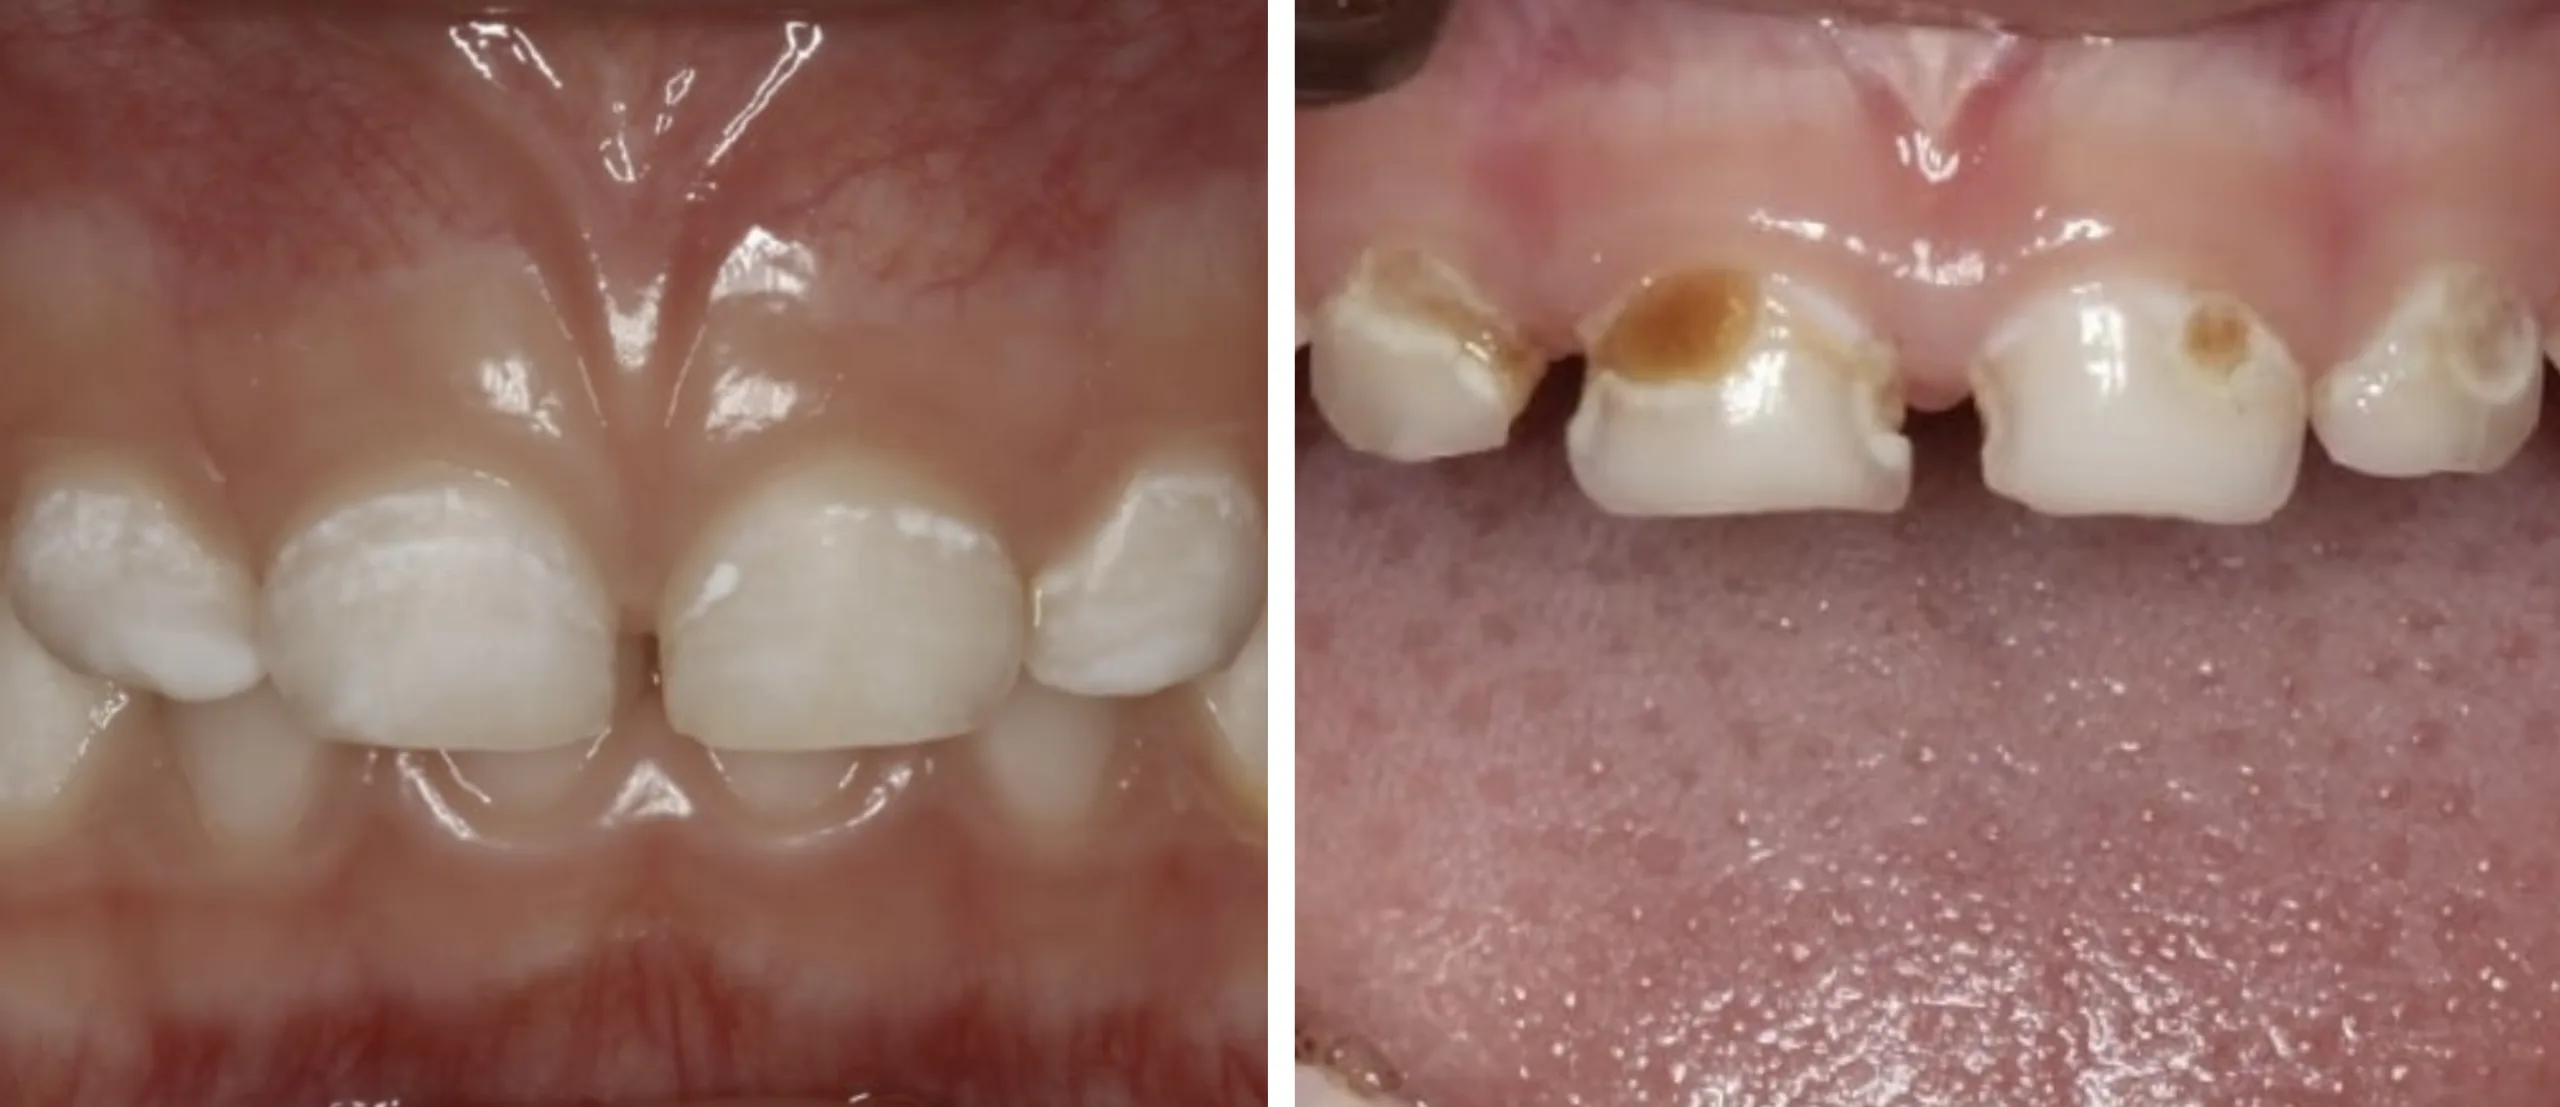

A Cárie Precoce da Infância inicia-se com uma discreta desmineralização — isto é, a presença de uma mancha branca e opaca no esmalte, sem cavidade —, junto à gengiva de um ou mais dentes da frente, superiores (incisivos superiores).

Se não for tratada atempadamente, poderá progredir rapidamente para cavidades, até causar uma destruição total da coroa do dente, nos casos mais graves.